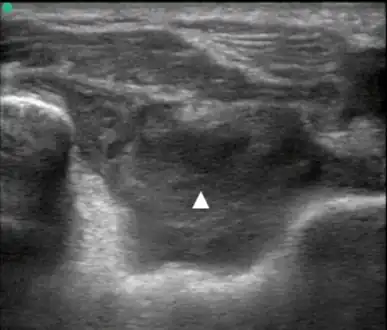

Lipohemarthrosis (blood and fat in the joint space) seen in a person with a subtle tibial plateau fracture. The arrow indicates a fluid level between the upper fat component and the lower blood component.